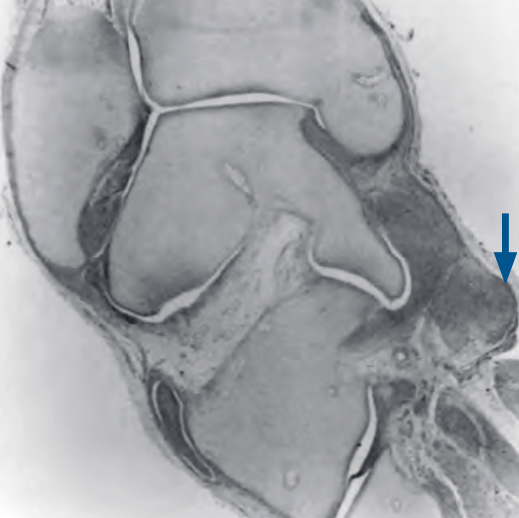

El tendón del tibial posterior, cuya inserción está engrosada en el pie equino varo, se alarga no solo al escafoides, sino también por la zona plantar al cuneiforme medial(5)(Figura 1), e incluso se describen fibras en la zona proximal del abductor del hallux unidas al propio tendón del tibial posterior(6).

Figura 1. Cambio anatómico. Imagen adaptada de estudios del Dr. Ponseti(5) en la que se observa el engrosamiento de los ligamentos de la zona posterointerna y el tendón tibial posterior (flecha azul) que llegan a la primera articulación tarsometatarsiana.